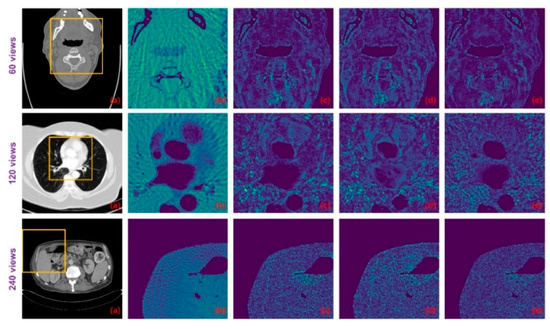

To investigate the degradation perception of the image-domain module, we compared the predicted critical-map of the spatial-attention block for the same image with different degradation levels, as shown in Figure 7. The first column is the ideal CT image, whilst the second, third and fourth columns represent the predicted critical-maps at 60 views, 120 views and 240 views, respectively. We zoomed in on the red square area and displayed it in color to observe the textual details. The edge information of the critical-map increases as the degradation decreases, which indicates that the reconstructed values of the contours are generally inaccurate and the later refining block should enhance the detail recovery and reconstruction. In the case of the large degradation level, the critical-map of the image is blurry, indicating that there are still small artifacts interfering in the flat region, which should be further removed in the refining block to improve the overall intensity recovery.

Figure 7. Examples of predicted critical-maps at 60 views, 120 views and 240 views.